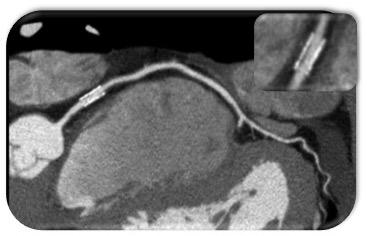

O músculo cardíaco é irrigado pelas artérias coronárias, que são vasos epicárdicos. Ponte miocárdica é uma anomalia congênita na qual um segmento da artéria coronária percorre um trajeto intramiocárdico com extensão e profundidade variáveis, ao invés de percorrer o seu trajeto epicárdico normal.